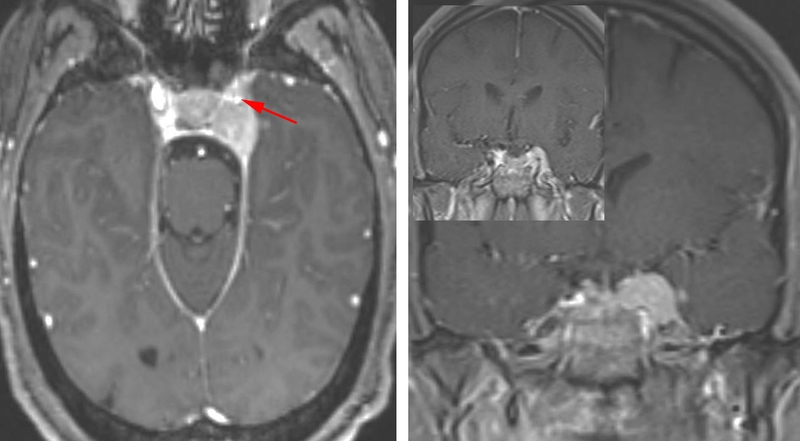

U màng não xoang hang là một loại của u màng não. Đây là những khối u hiếm gặp, gây ảnh hưởng đến vùng xoang hang của bạn. Khu vực này phụ trách kiểm soát các chuyển động của mắt và cảm giác của khuôn mặt.

Do u màng não xoang hang là một loại của u màng não nên các đặc tính cũng tương tự như u màng não nói chung. Về tiến triển, u màng não xoang hang cũng tiến triển âm thầm nên khi phát hiện, khối u thường có kích thước đủ lớn để gây chèn ép khu vực xung quanh, bao gồm não, dây thần kinh và mạch máu lân cận. Thể bệnh này có thể gây nên tình trạng nhìn đôi, chóng mặt và cảm giác đau tại vùng mặt tương ứng. Các triệu chứng của bệnh cũng có thể khó phát hiện và bị nhầm lẫn với các tình trạng sức khỏe khác thường được coi là do tình trạng lão hóa của ở người cao tuổi gây nên. Các phương pháp điều trị u màng não xoang hang cũng tương tự như với u màng não, đó là theo dõi tình trạng tiến triển của bệnh, phẫu thuật loại bỏ khối u, xạ trị, chăm sóc giảm nhẹ hoặc có thể là hóa trị.